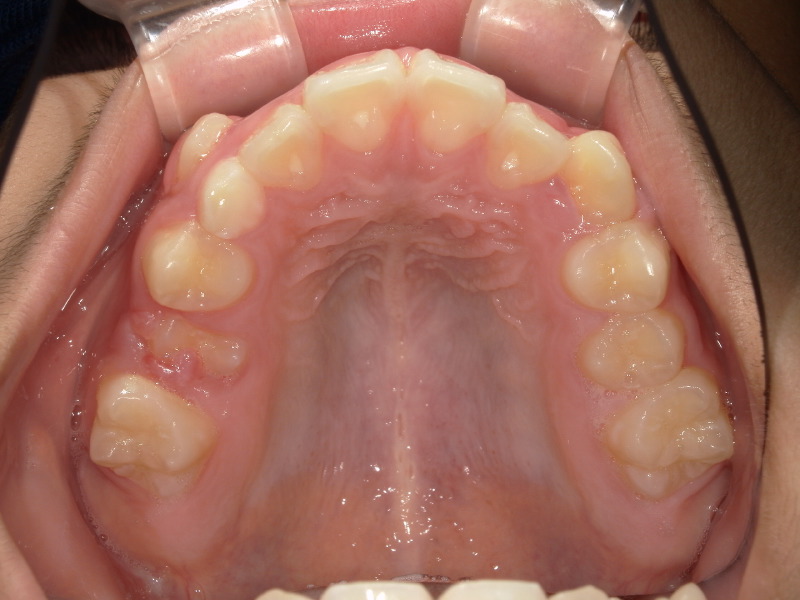

この男の子の主訴にもある八重歯、この歯は大体9ー10歳頃に生え変わりが起こる歯です。

写真でもあるように唇側の歯茎から出てきており、大きさもあるので顎のアーチの中には入らなさそうです。

このまま放置しているとこの歯は唇側に留まってしまい、いわゆる八重歯と呼ばれる歯になります。